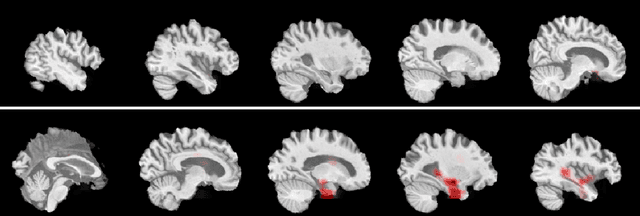

Abstract:In this work, deep learning techniques for brain age prediction from magnetic resonance images are investigated, aiming to assist in the identification of biomarkers of the natural aging process. The identification of biomarkers is useful for detecting an early-stage neurodegenerative process, as well as for predicting age-related or non-age-related cognitive decline. Two techniques are implemented and compared in this work: a 3D Convolutional Neural Network applied to the volumetric image and a 2D Convolutional Neural Network applied to slices from the axial plane, with subsequent fusion of individual predictions. The best result was obtained by the 2D model, which achieved a mean absolute error of 3.83 years. -- Neste trabalho s\~ao investigadas t\'ecnicas de aprendizado profundo para a predi\c{c}\~ao da idade cerebral a partir de imagens de resson\^ancia magn\'etica, visando auxiliar na identifica\c{c}\~ao de biomarcadores do processo natural de envelhecimento. A identifica\c{c}\~ao de biomarcadores \'e \'util para a detec\c{c}\~ao de um processo neurodegenerativo em est\'agio inicial, al\'em de possibilitar prever um decl\'inio cognitivo relacionado ou n\~ao \`a idade. Duas t\'ecnicas s\~ao implementadas e comparadas neste trabalho: uma Rede Neural Convolucional 3D aplicada na imagem volum\'etrica e uma Rede Neural Convolucional 2D aplicada a fatias do plano axial, com posterior fus\~ao das predi\c{c}\~oes individuais. O melhor resultado foi obtido pelo modelo 2D, que alcan\c{c}ou um erro m\'edio absoluto de 3.83 anos.